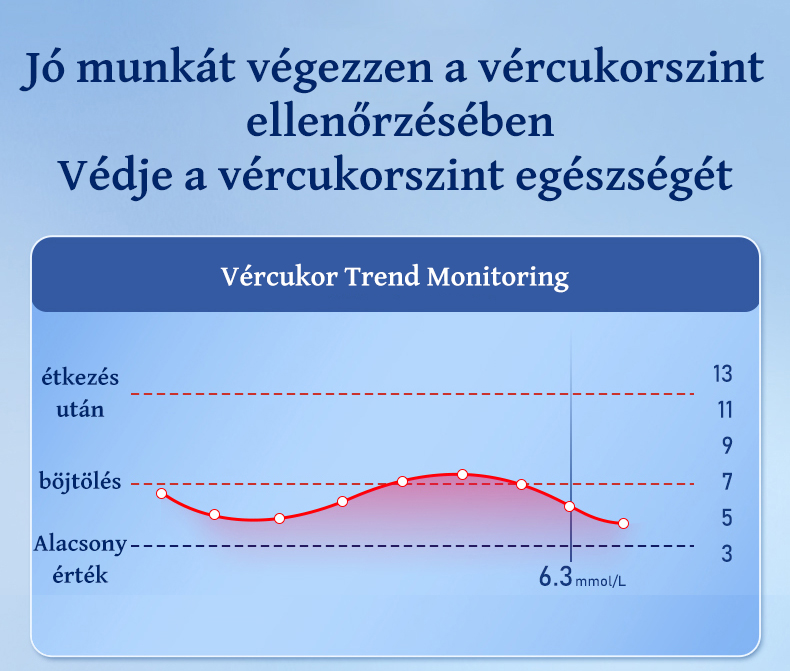

Nagy pontosságú intelligens egészségmegfigyelő óra

A szív- és érrendszeri és agyi érrendszeri betegségek "magas morbiditással, magas rokkantsággal, magas magas halálozási arány, magas kiújulási arány és számos szövődmény"